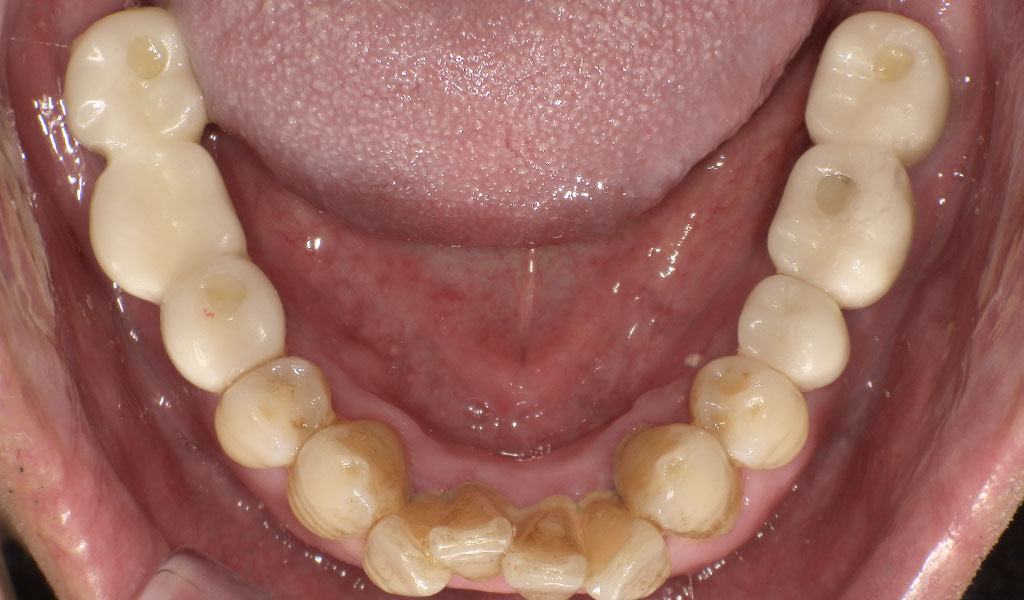

After(左下6,7番、右下5,6,7番)

60代男性・横浜市在住。歯周病により歯がぐらついていたため、当院にて左上6番、左下6,7番、右下5,6,7番を抜歯後、インプラント治療。人工歯はジルコニア人工歯。スクリューリテインにて固定しました。歯周病菌の数が多いため、歯周内科治療も実施しました。

インプラントと骨がしっかり結合するまで3ヶ月待ち、また、歯周内科による治療が終わった上で、インプラントの上に人工の歯を被せる治療を行いました。